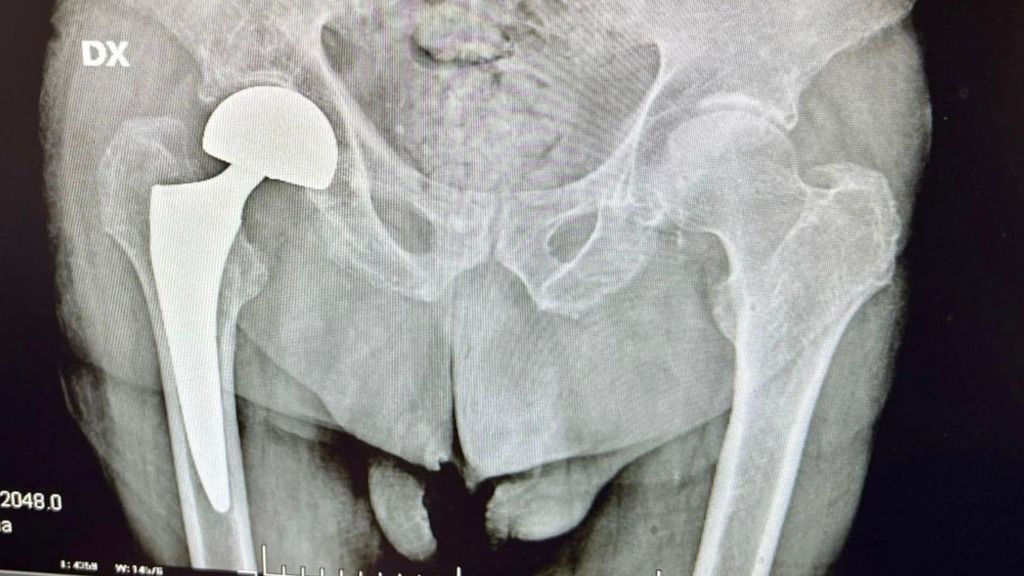

Lo scorso aprile, a causa di una caduta accidentale avvenuta in casa, il paziente ha riportato una frattura mediale scomposta del collo femorale destro e un trauma cranico non commotivo. Dopo essere stato ricoverato nella U.O.C. di Ortopedia e Traumatologia, entro le 48 ore, come da linee guida nazionali e da protocollo aziendale, è stato sottoposto ad un delicato intervento chirurgico di protesi all’anca destra eseguito dal Dottore Gianluca Melito, chirurgo ortopedico e dirigente medico presso il Grande Ospedale Metropolitano.

Un intervento complesso, perfettamente eseguito e che ha visto la degenza di Ferdinando presso il reparto della stessa U.O.C. di Ortopedia e Traumatologia.